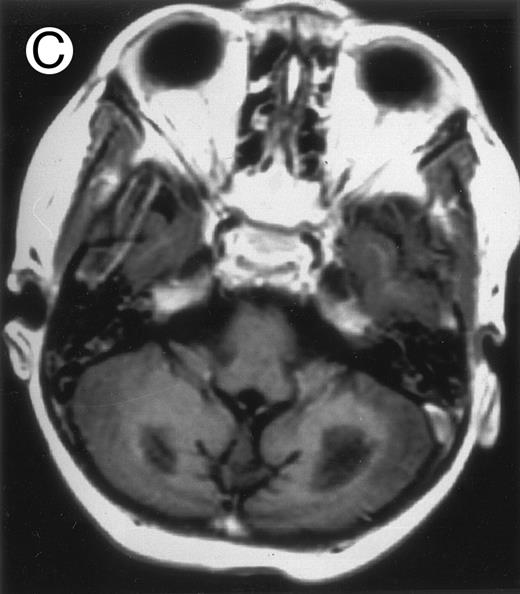

Among the nine children with initial neurological symptoms, seizures were the most frequent initial symptom in the youngest patients, whereas ataxia was found in the two oldest patients (46 and 58 months old, respectively) (Table 1). All nine patients had the same CSF abnormalities as patients with meningitis only. Eight of these nine patients had a neuroradiological study performed at the time of their first neurological symptoms (Table 1). The two most frequent lesions were focal necrosis with parenchymal volume loss and atrophy (Fig 2A and C) and white matter abnormalities (Fig 2B). Several small focal lesions with hypersignal at MR imaging that enhanced after administration of gadopentate dimeglumine (or contrast on CT scan) were also observed in two cases.

Three different aspects of brain imaging in HLH patients. (A) CT scan of a 3-month-old baby showing a large subdural effusion, several necrotic areas and hypodensities of the white matter. (B) Brain magnetic resonance of a 14-month-old boy showing large confluent areas of hypersignal in T2-weighted images. (C) Large symmetrical necrotic areas of cerebellar white matter in a 41/2-year-old girl (MRI).